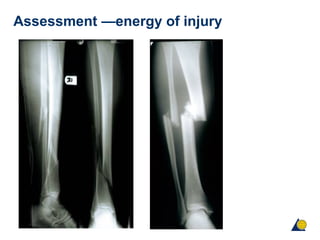

Assessment—energy of injury

Assessment —energy of injury